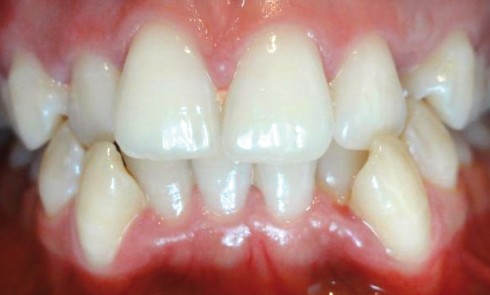

Présentation du cas Il s’agit d’un patient adulte de 28 ans (fig. 1) présentant une classe I, une dysharmonie dento-maxillaire (DDM),...